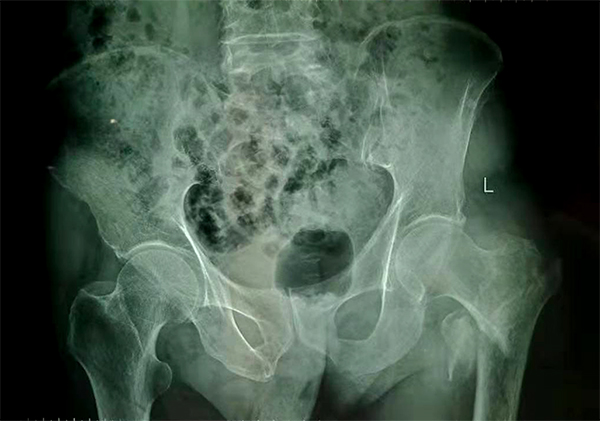

經(jīng)檢查拍片診斷為左股骨粗隆間粉碎性骨折,收入骨科住院,張爺爺既往有“2型糖尿病”病史10余年,還有“腦梗塞”病史5年,導(dǎo)致左側(cè)肢體偏癱。

手術(shù)前

手術(shù)后

9月10日上午,骨科順利完成張爺爺?shù)淖蠊晒谴致¢g骨折髓內(nèi)釘內(nèi)固定術(shù)。手術(shù)過(guò)程中麻醉平穩(wěn),術(shù)中出血量少,骨折手術(shù)時(shí)間持續(xù)一個(gè)多小時(shí)。